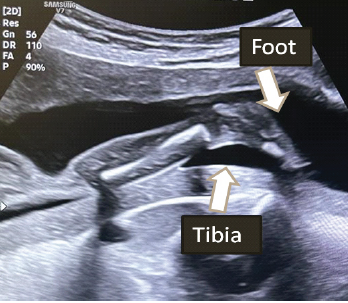

An Observational Study on Pre-natal Diagnosis of Congenital Talipes Equinovarus